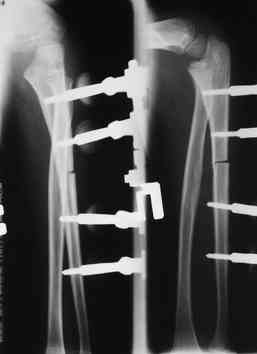

Иллюстрация к лечению застарелого повреждения Монтеджиа

Пациентка клиники детской травматологии ЦИТО

На рентненграмме видна деформация локтевой кости на границе верхней и средней трети. Ведь там был перелом.

Уважаемые коллеги, кто-нибудь еще видит здесь застарелое повреждение Монтеджи? Может мне показалось?

Многоуважаемые коллеги, всем большое спасибо!!! Да, здесь было повреждение Монтеджиа, когда нарисовал скиаграмму все стало понятно. Мне очень понравились рекомендации Константина Требухина, только немножко видоизменил; я считал так, если деформацию исправить то локт/кость должна удлиниться, и во вторых, если на аппарате низвести лучевую кость, то может наступить позиционное несоответствие в дистальном радиоульнарном сочленении. 28.02.08г операция - шарнирная остеотомия локтевой кости на уровне деформации, далее вскрыт плечелучевой сустав, удалены рубцовые тканы, после исправления варусной деформации и создания физиологического изгиба локтевой кости головка луча легко вправился, из части рубцовой ткани сделана пластика кольцевндной связки, трансартикулярная фиксация спицей, локтевая кость двумя спицами.